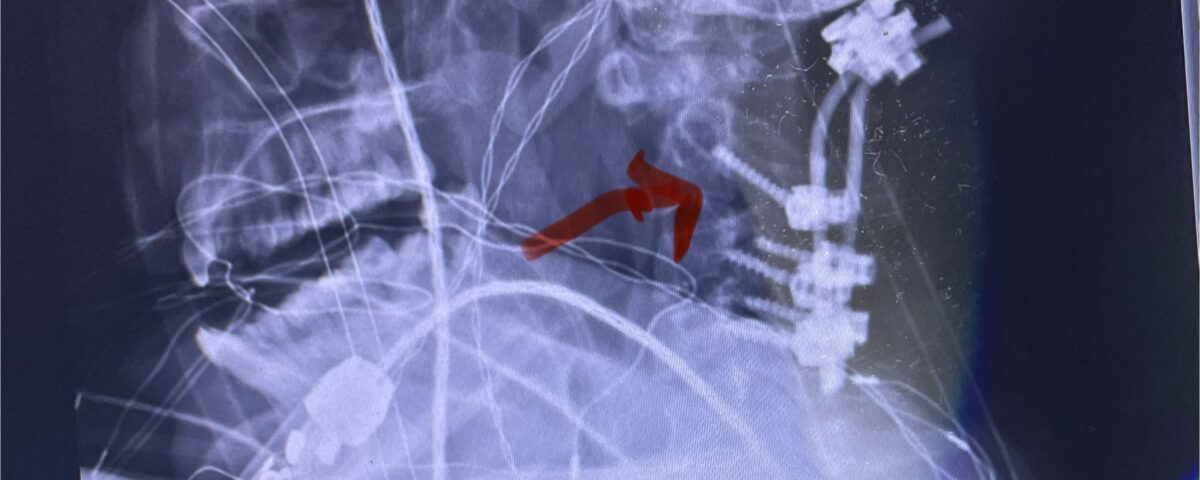

Cervical x-rays revealed a significantly increased atlanto-axial interval (Fig. 5) On review of her imaging studies it was noted that the right C2 isthmus was very thinned by the vertebral foramen (Figs 6a, b, and c) which would make an attempt at placing a C2 pars screw dangerous. A decision was made to perform an occipital-cervical fusion because only possible unilateral fixation and an extensive C1 laminectomy to be performed eliminating a fixation point if a more traditional C1-C2 was performed. Even if C1 lateral mass screws were able to be placed one could only perform a unilateral screw construct fixation to C2. We performed an occipital cervical fusion down to C4 to get enough inferior fixation and C1 laminectomy. The decompression went well. We placed a left unilateral pars screw and bilateral C3 and C4 lateral mass screws. We placed three 12 mm screws in the midline keel (Fig. 7). Postoperatively the patient had all around improvement in her symptoms and did not qualify for rehab. Her post op films at 6 weeks (Fig. 8)

Fig. 8: Intraoperative photograph demonstrating occipital-cervical construct and C1 laminectomy (blue dot). Note the 3 screws in the midline keel (blue arrow)